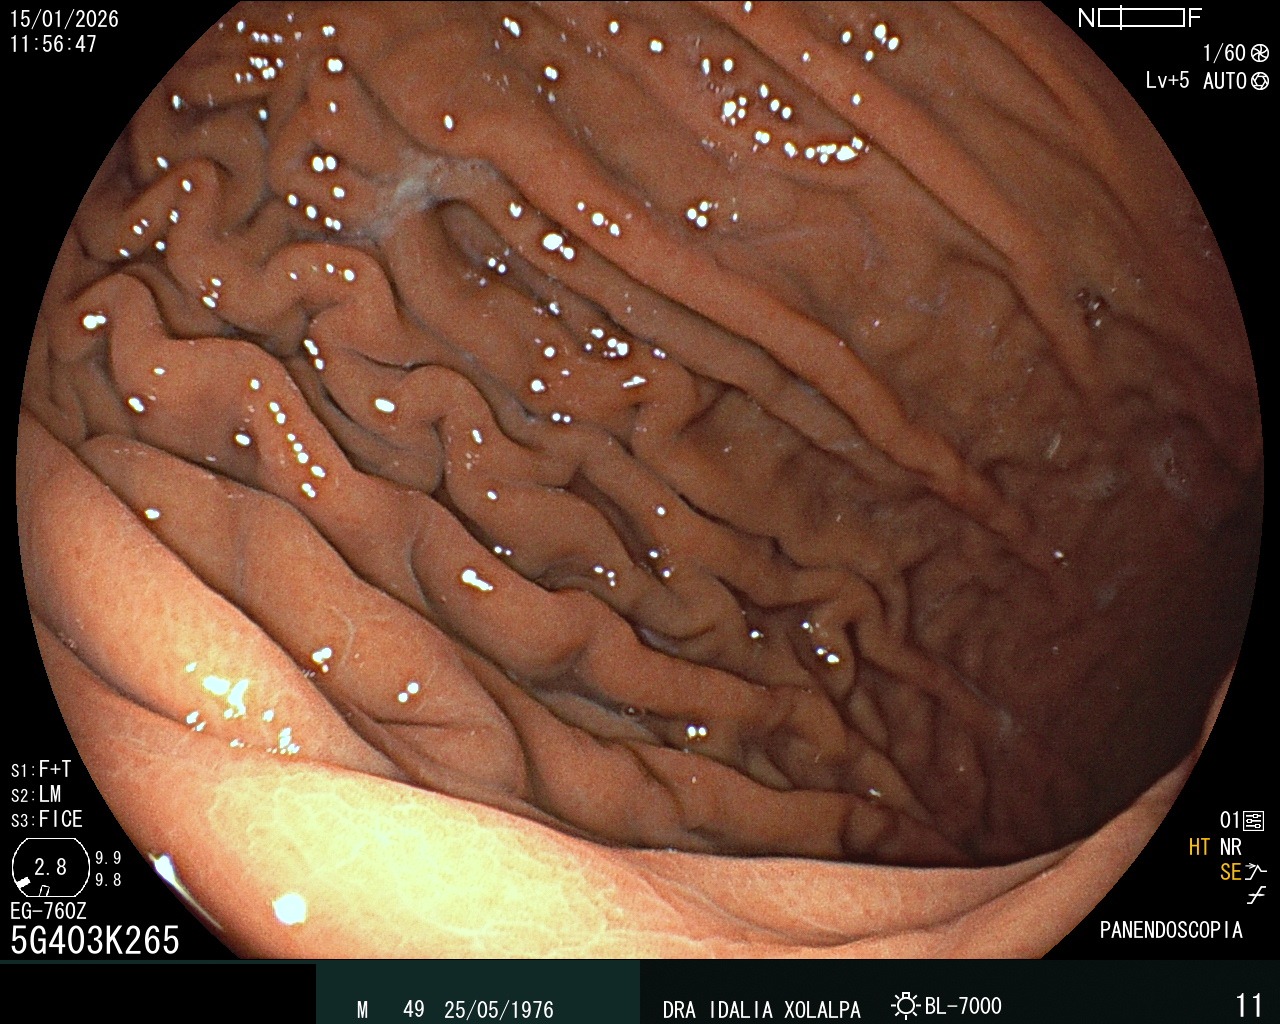

Colon Normal

Vista de un colon sano durante colonoscopia